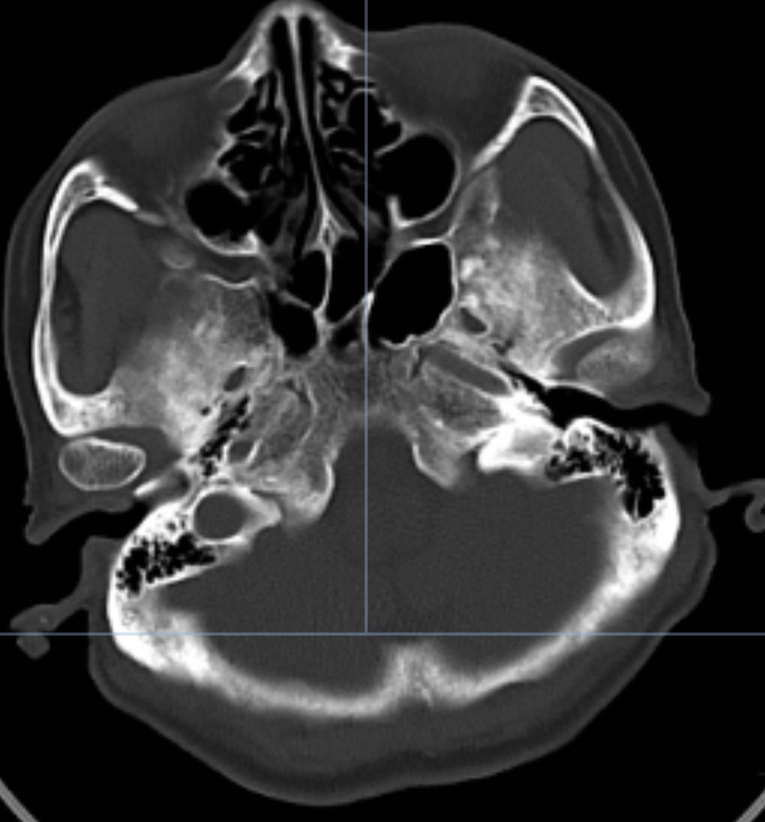

患者70岁女性,以右侧口角电击样疼痛6月为主诉入院,口服卡马西平早期有效,后增加药量后效果不佳,药物副作用症状明显,查体可见患者痛苦面容,消瘦,进食困难,不敢言语,言必痛。评估病情后家属要求行球囊压迫术。

术后自觉右侧颜面部麻木,右侧口角疼痛不明显。